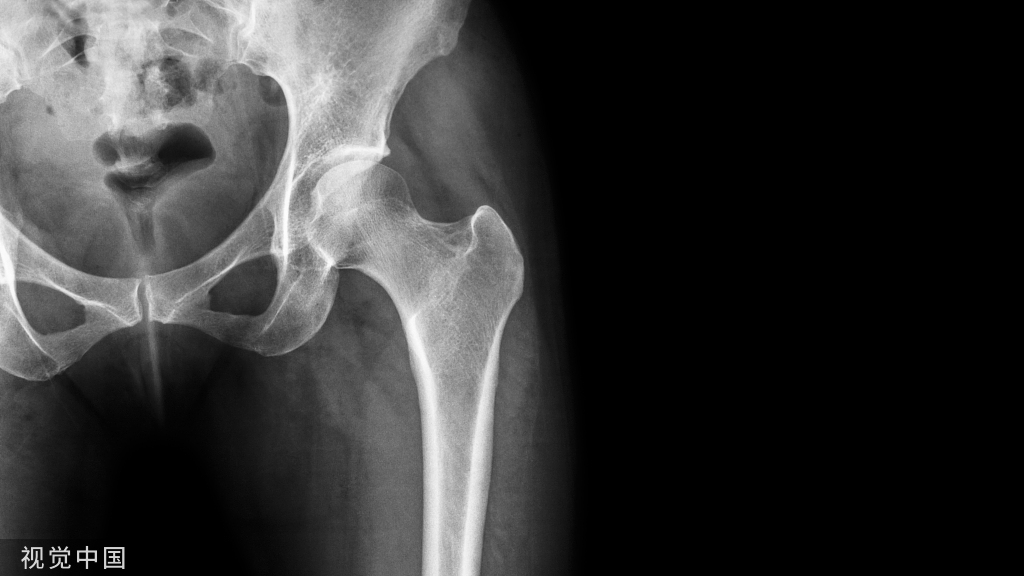

髋关节前外侧入路是髋关节手术中被广泛应用的手术入路,最先由Bardenheuer等描述,经Smith-Petersen改良而得名。该切口始于髂嵴中部,向前至髂前上棘,然后转向髌骨外缘方向,向远端延伸10~12cm(图1)。该入路主要利用两个神经界面:浅层经缝匠肌(股神经支配)和阔筋膜张肌(臀上神经支配)间隙进入(图2),深层则经股直肌(股神经支配)和臀中肌(臀上神经支配)之间暴露(图3)。